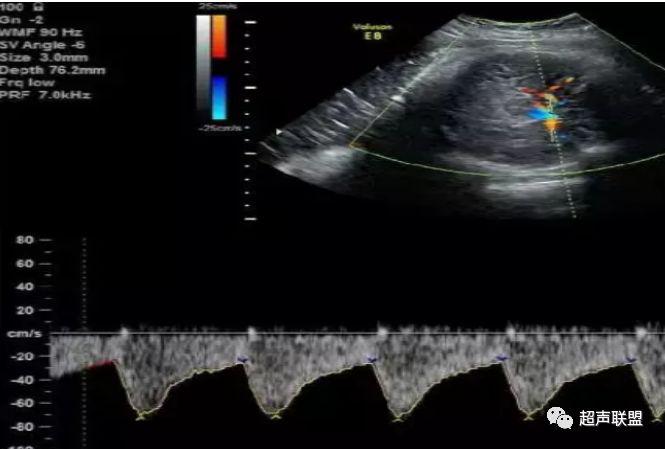

1 胎儿脐动脉测定

缺氧首先出现的变化是舒张末期血流降低,S/D值、RI值和PI值升高。当缺氧进入再分配晚期时,可逐渐出现舒张期血流减少、舒张期血流缺失。失代偿期出现脐动脉血液逆流,舒张期血流倒置。

图1 正常脐动脉血流频谱

图2 脐动脉舒张期血流消失或反向